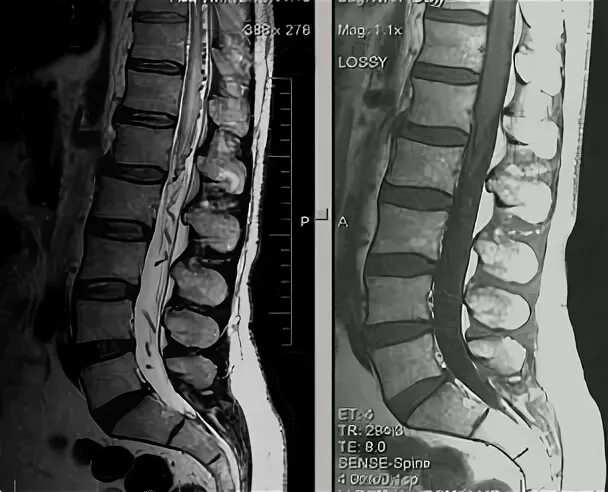

Деформация дурального мешка поясничного